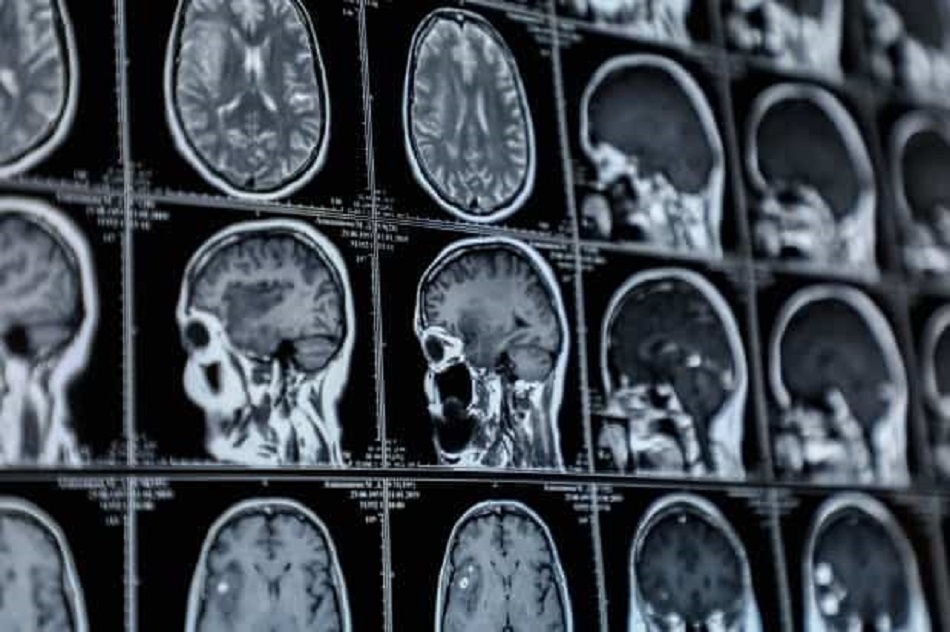

ЭМДҮЗ-ийн 2022 оны нэгдүгээр тогтоолоор тархины хоргүй хавдрын эмийн эмчилгээг 470 мянган төгрөг, мэс заслын тусламж үйлчилгээний хүндрэл, хэрэглэгдэх багаж хэрэгслээс хамаарч 4.3 - 15.6 сая төгрөг байх бөгөөд үүний 85 хувийг ЭМД-ын сангаас хариуцан төлөхөөр зохицуулсан.